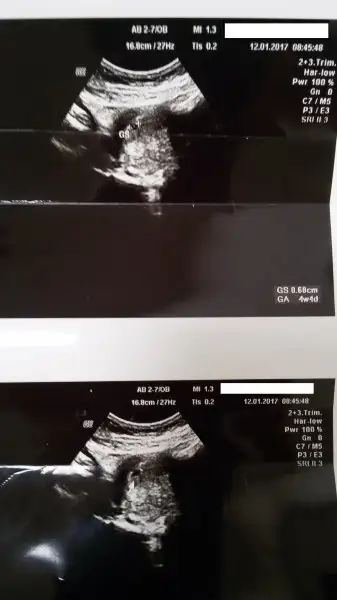

bi de şu ultrason resimlerindeki değerleri okuyup anlayabilsem daha iyi olacak

Sağ altta yazanlar önemli şuan ga gebelik haftası 4 hafta 4 günlük canım gs de gebelik kesesi o da 0.68 cm yarım santimden biraz büyük işte :)))) şimdi on gün sonra crl görülecek yani bebeğin o da yazacak orda

4 hafta 4günlük bir bebek için normal mi acaba kesenin boyu